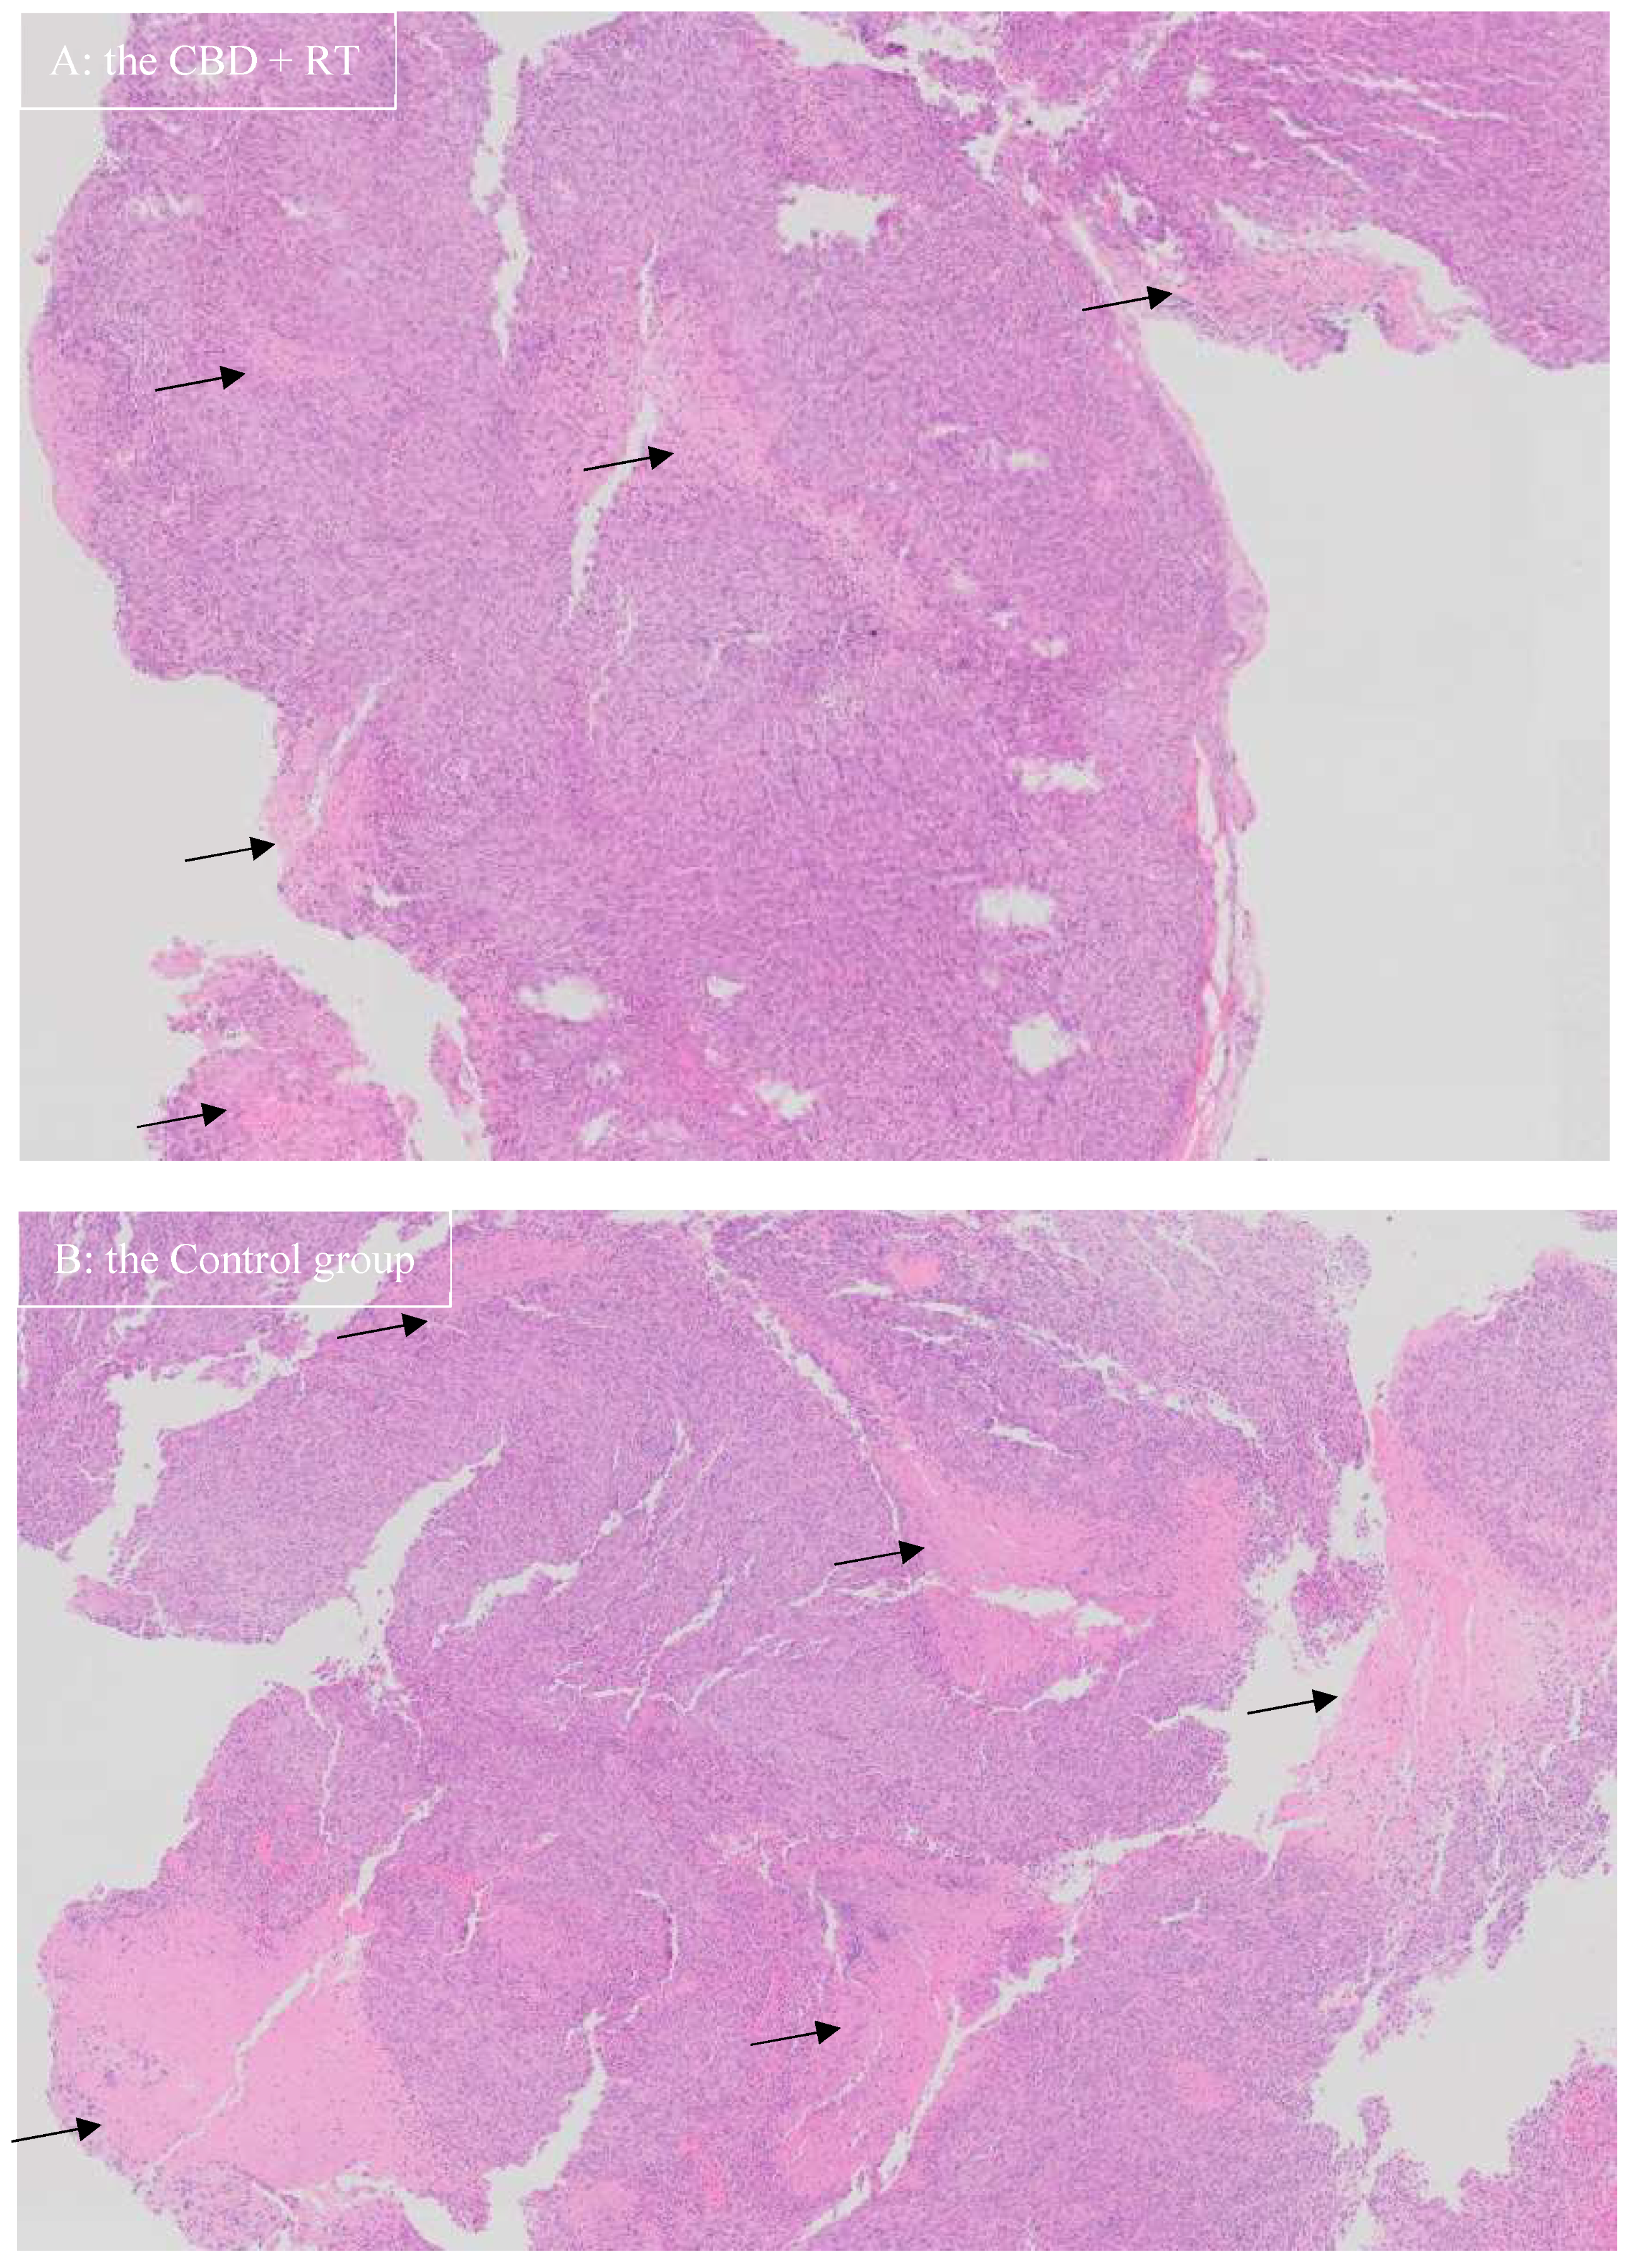

3. Results